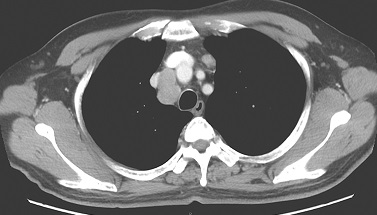

1小时条评论49岁男性,受凉后出现阵发性咳嗽,咳少许白色黏液痰,按上呼吸道感染对症治疗后症状部分缓解,治疗后发热1个月,如何诊治? 一、病情摘要 1.基本情况 男性患者,49岁,因咳嗽半年,发热1个月,于2005年9月入院。患者于半年前,受凉后出现阵发性咳嗽,咳少许白色...